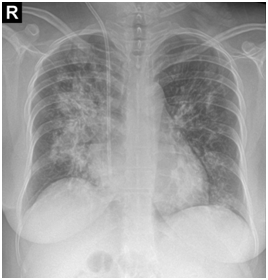

After one-month, the pulse-therapy of cyclophosphamide is repeated, in the same day, she presented by hemorrhagic cystitis (U/A: blood: +4, RBC: many, WBC: 2-3) and one-day later she complains dyspnea and hemoptesis. Also on CBC has been pancytopenic (WBC: 2300, Hb: 4.9, MCV: 94, Plt: 42000). So she’s admitted to hospital with probability relapsing and she takes the one-time pulse of Methyl-Prednisolone and plasmaphresis is done. CXR, CT-scan and bronchoscopy are repeated and bronchoscopy reveals the hemorrhagic alveolar pattern (Figure 1).

Figure 1 CXR, CT-scan and bronchoscopy are repeated and bronchoscopy reveals the hemorrhagic alveolar pattern.